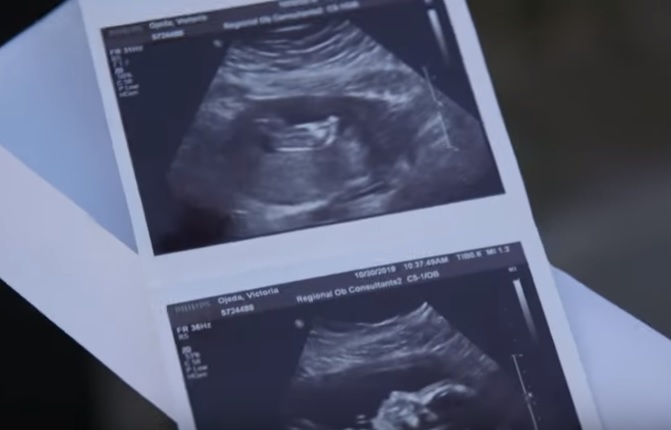

Tânăra de 20 de ani, Tory Ojeda, nu dorește să facă un test de paternitate, deoarece îi iubește pe toți cei patru bărbați pe care îi are alături. Diferențele sunt excluse în familia lor, iar cei patru bărbați sunt încântați de modul în care conviețuiesc. Mai mult decât atât, tânăra de 20 de ani trăiește deja cu trei dintre cei patru bărbați pe care îi iubește. Aceștia locuiesc în Jacksonville, Florida, și este mai pregătită ca niciodată pentru a intra, în acest fel, în ”istoria relațiior poliamoroase”.

Conform The Mirror, cei patru bărbați pe care îi iubește sunt: Marc, Travis, Ethan și Cristopher. Aceasta crede că tatăl biologic al fetiței care se va naște în februarie 2020 ar fi Cristopher, cel din urmă.